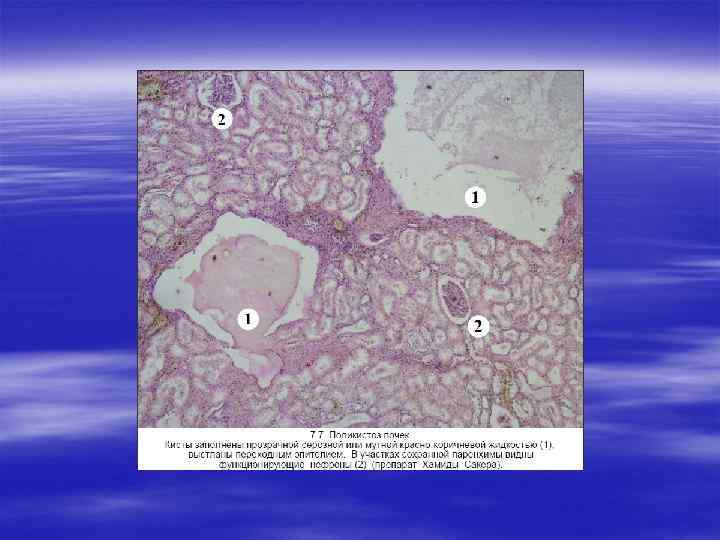

ПОЛИКИСТОЗ ПОЧЕК § Заболевания почек, связанные с образованием кист, представ ляют собой гетерогенную группу и ведут к развитию хронической почечной недостаточности. Кистозные процессы могут носить врожденный и приобретенный характер. Кисты бывают одиночны ми и множественными.

§ Выделяют поликистоз почек новорожденных и поликистоз почек у взрослых. § Поликистоз почек новорожденных наследуется по аутосомно рецессивному типу и обнаруживается уже при рождении. Почки новорожденных отличаются большими размерами, наличием множества кист, выстланных плоским или кубическим эпителием. Кистоз охватывает около 90 % паренхимы почек. Аномалия возникает в эмбриональном периоде при несвоевременном и непра вильном соединении секреторной и экскреторной части почек. Обнаруживается недоразвитие канальцев и отсутствие соединения их с собирательными трубочками, часть канальцев запустевает и превращается в ретенционные кисты. Паренхима почек атрофируется. Некоторые кисты имеют вид слепых мешочков (закрытые кисты).

§ Поликистоз почек у взрослых наследуется по аутосомно доминантному типу, при рождении отсутствует и развивается в последующие годы медленно. Первые симптомы появляются в подростковом периоде и связаны с кистозной дилатацией функционирующих нефронов (открытые кисты). Кисты занимают примерно 10 % паренхимы. Поликистоз почек у взрослых осложняется хронической почечной недостаточностью у 6— 12 % больных. Почки резко увеличены, масса каждой почки достигает 4 кг.